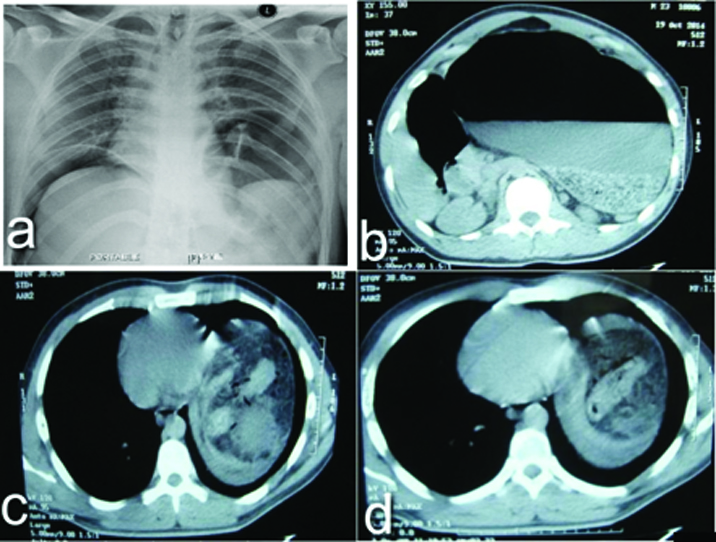

A 23-year-old male patient presented with abdominal pain and vomiting for two days duration. The pain was progressively increasing in severity and generalized to all quadrants of the abdomen over 24 hours. Vomiting was non bilious and contained food particles. He was initially evaluated at a local hospital where Intravenous fluids were given, ryles tube was inserted which had a haemorrhagic aspirate and a Contrast Enhanced Computed Tomography (CECT) of the abdomen was done and the patient was referred to our centre. At presentation, patient had a pulse rate of 140/min, Blood pressure of 100/60, Respiratory rate of 28/ min. Per abdominal examination revealed board like rigidity with obliteration of liver dullness. Patient was resuscitated with intravenous fluids and oxygen by mask. All the lab parameters were sent. Chest X ray erect view showed air under the diaphragm bilaterally with an elevation of the left lobe of the diaphragm compared to the right [Table/Fig-1a]. CECT abdomen done outside was reported as gross distension of the stomach and air within the mesenteric vessels and portal venous system suspicious of bowel infarction [Table/Fig-1b-d]. Leukocyte count was 12,200cells/cumm, serum creatinine - 2.6mg/dl, serum bilirubin - 1.4mg/dl, with haemoglobin of 16.6g/dl.

(a) Chest X-Ray showing air under diaphragm on the right side and herniation of the stomach into the chest on the left side (b-d) CECT abdomen showing air in the mesentery in the herniated portion with gastric outlet obstruction.